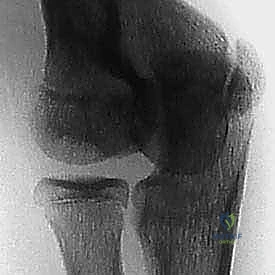

- الأشعة السينية (X-rays): هي الخطوة الأولى. تُظهر الأشعة السينية التغيرات العظمية، التفتت في داء بانر، أو التجاويف والأجسام الحرة في الـ OCD. يحرص الدكتور هطيف على أخذ وضعيات متعددة (أمامية، جانبية، ومائلة) لضمان عدم تفويت أي تفصيل.

| التشخيص بالأشعة السينية | الكابيتيليوم يظهر متفتتاً وغير منتظم بالكامل | آفة موضعية (حفرة) أو جسم حر واضح في المفصل |